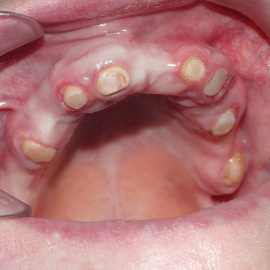

Bezzębie całkowite górne. Początkowo wykonane na mieście mosty całoceramiczne wydawały sie sukcesem, ale po roku pojawiły sie obrzęki i krwawienie z dziąseł. Pacjentka zgłosiła się do leczenia. Usunięto wszystkie zęby w szczęce. Sterowana regeneracja tkanek kości wyrostka, modelowanie kształtu i objętości tkanek miękkich, mosty porcelanowe przykręcane do implantów. Zadowalający wynik anatomiczny i estetyczny.